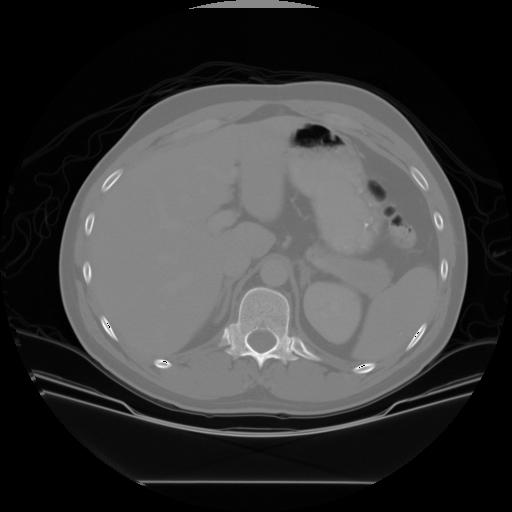

The main goal of this assignment is to find organs of interest in CT images, using techniques of binary vision in Matlab. The organs of interest are the kidneys, the liver, and the spleen, as shown below.